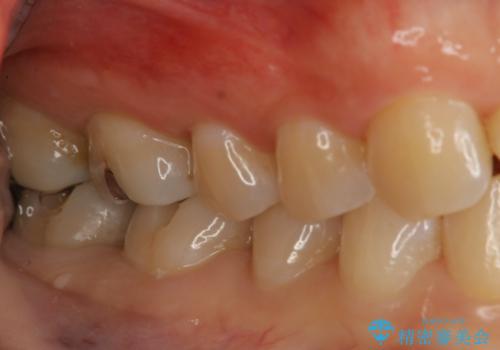

奥歯を綺麗にしたい

- 右下6・7番の咬合面に詰められた保険材料が劣化していたので、審美性・切削量を考慮しセラミックインレー治療を選択しました。

劣化した保険材料・虫歯を全て除去した上で形成しています。